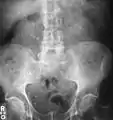

Calcium-containing stones are relatively radiodense, and they can often be detected by a traditional radiograph of the abdomen that includes the kidneys, ureters, and bladder (KUB film).[58] KUB radiograph, although useful in monitoring size of stone or passage of stone in stone formers, might not be useful in the acute setting due to low sensitivity.[59] Some 60% of all renal stones are radiopaque.[60][61] In general, calcium phosphate stones have the greatest density, followed by calcium oxalate and magnesium ammonium phosphate stones. Cystine calculi are only faintly radiodense, while uric acid stones are usually entirely radiolucent.[62]

Otherwise a noncontrast helical CT scan with 5 millimeters (0.2 in) sections is the diagnostic method to use to detect kidney stones and confirm the diagnosis of kidney stone disease.[16][56][60][65][7] Near all stones are detectable on CT scans with the exception of those composed of certain drug residues in the urine,[58] such as from indinavir.

Where a CT scan is unavailable, an intravenous pyelogram may be performed to help confirm the diagnosis of urolithiasis. This involves intravenous injection of a contrast agent followed by a KUB film. Uroliths present in the kidneys, ureters, or bladder may be better defined by the use of this contrast agent. Stones can also be detected by a retrograde pyelogram, where a similar contrast agent is injected directly into the distal ostium of the ureter (where the ureter terminates as it enters the bladder).[60]